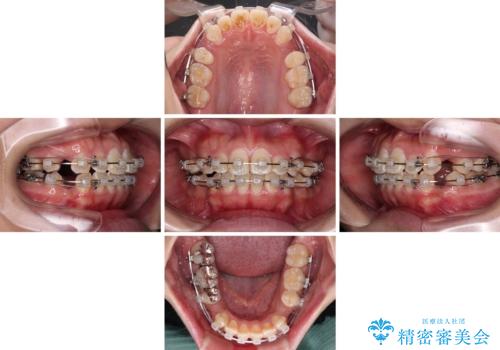

- クリアブラケット

- 2年2ヶ月

むし歯のリスクが高かったため、治療が長期化しないように心がけました。